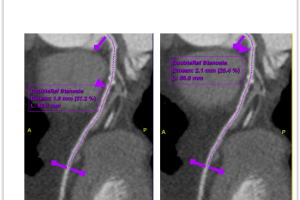

MSCT koronarografija je brza, precizna i neinvazivna metoda snimanja koja nam omogućava jasan uvid u stanje vaših koronarnih arterija. Pomoću najsavremenije CT tehnologije, možemo detaljno analizirati protok krvi i identificirati eventualna suženja ili blokade.

1. Rano otkrivanje i prevencija: MSCT koronarografija nam omogućava identifikaciju potencijalnih problema prije nego što postanu ozbiljni. Rana dijagnostika omogućava pravovremene intervencije i prilagodbe načina života kako biste očuvali zdravlje svog srca dugoročno.

3. Precizna dijagnostika: Najsavremenija tehnologija omogućuje nam otkrivanje čak i najmanjih promjena u koronarnim arterijama.